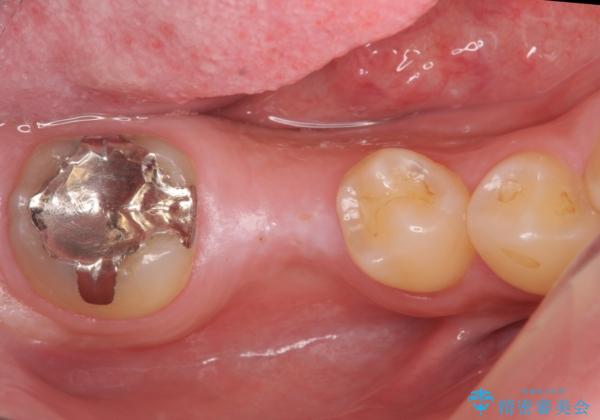

- 右下の奥歯にインプラントを入れたいと来院。

抜歯から時間が経っており、骨が十分あったためすぐにインプラントを入れることが可能でした。骨も補う必要がありませんでした。

手術が怖いとのことで、外科手術時には静脈麻酔を行い、眠っている間に手術が終わるようにしました。

インプラントの術式は比較的単純で、難しくないですが、予後を見据えて角化歯肉を増やす手間をかけることが大変重要です。

インプラント手術時に同時に親知らずの抜歯も行い、腫れや痛みなどを1度で終わらせるようにしました。